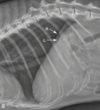

On lateral radiographs, the right diaphragmatic crus can be identified by its:

B

3

LL or RL?

LL

RL